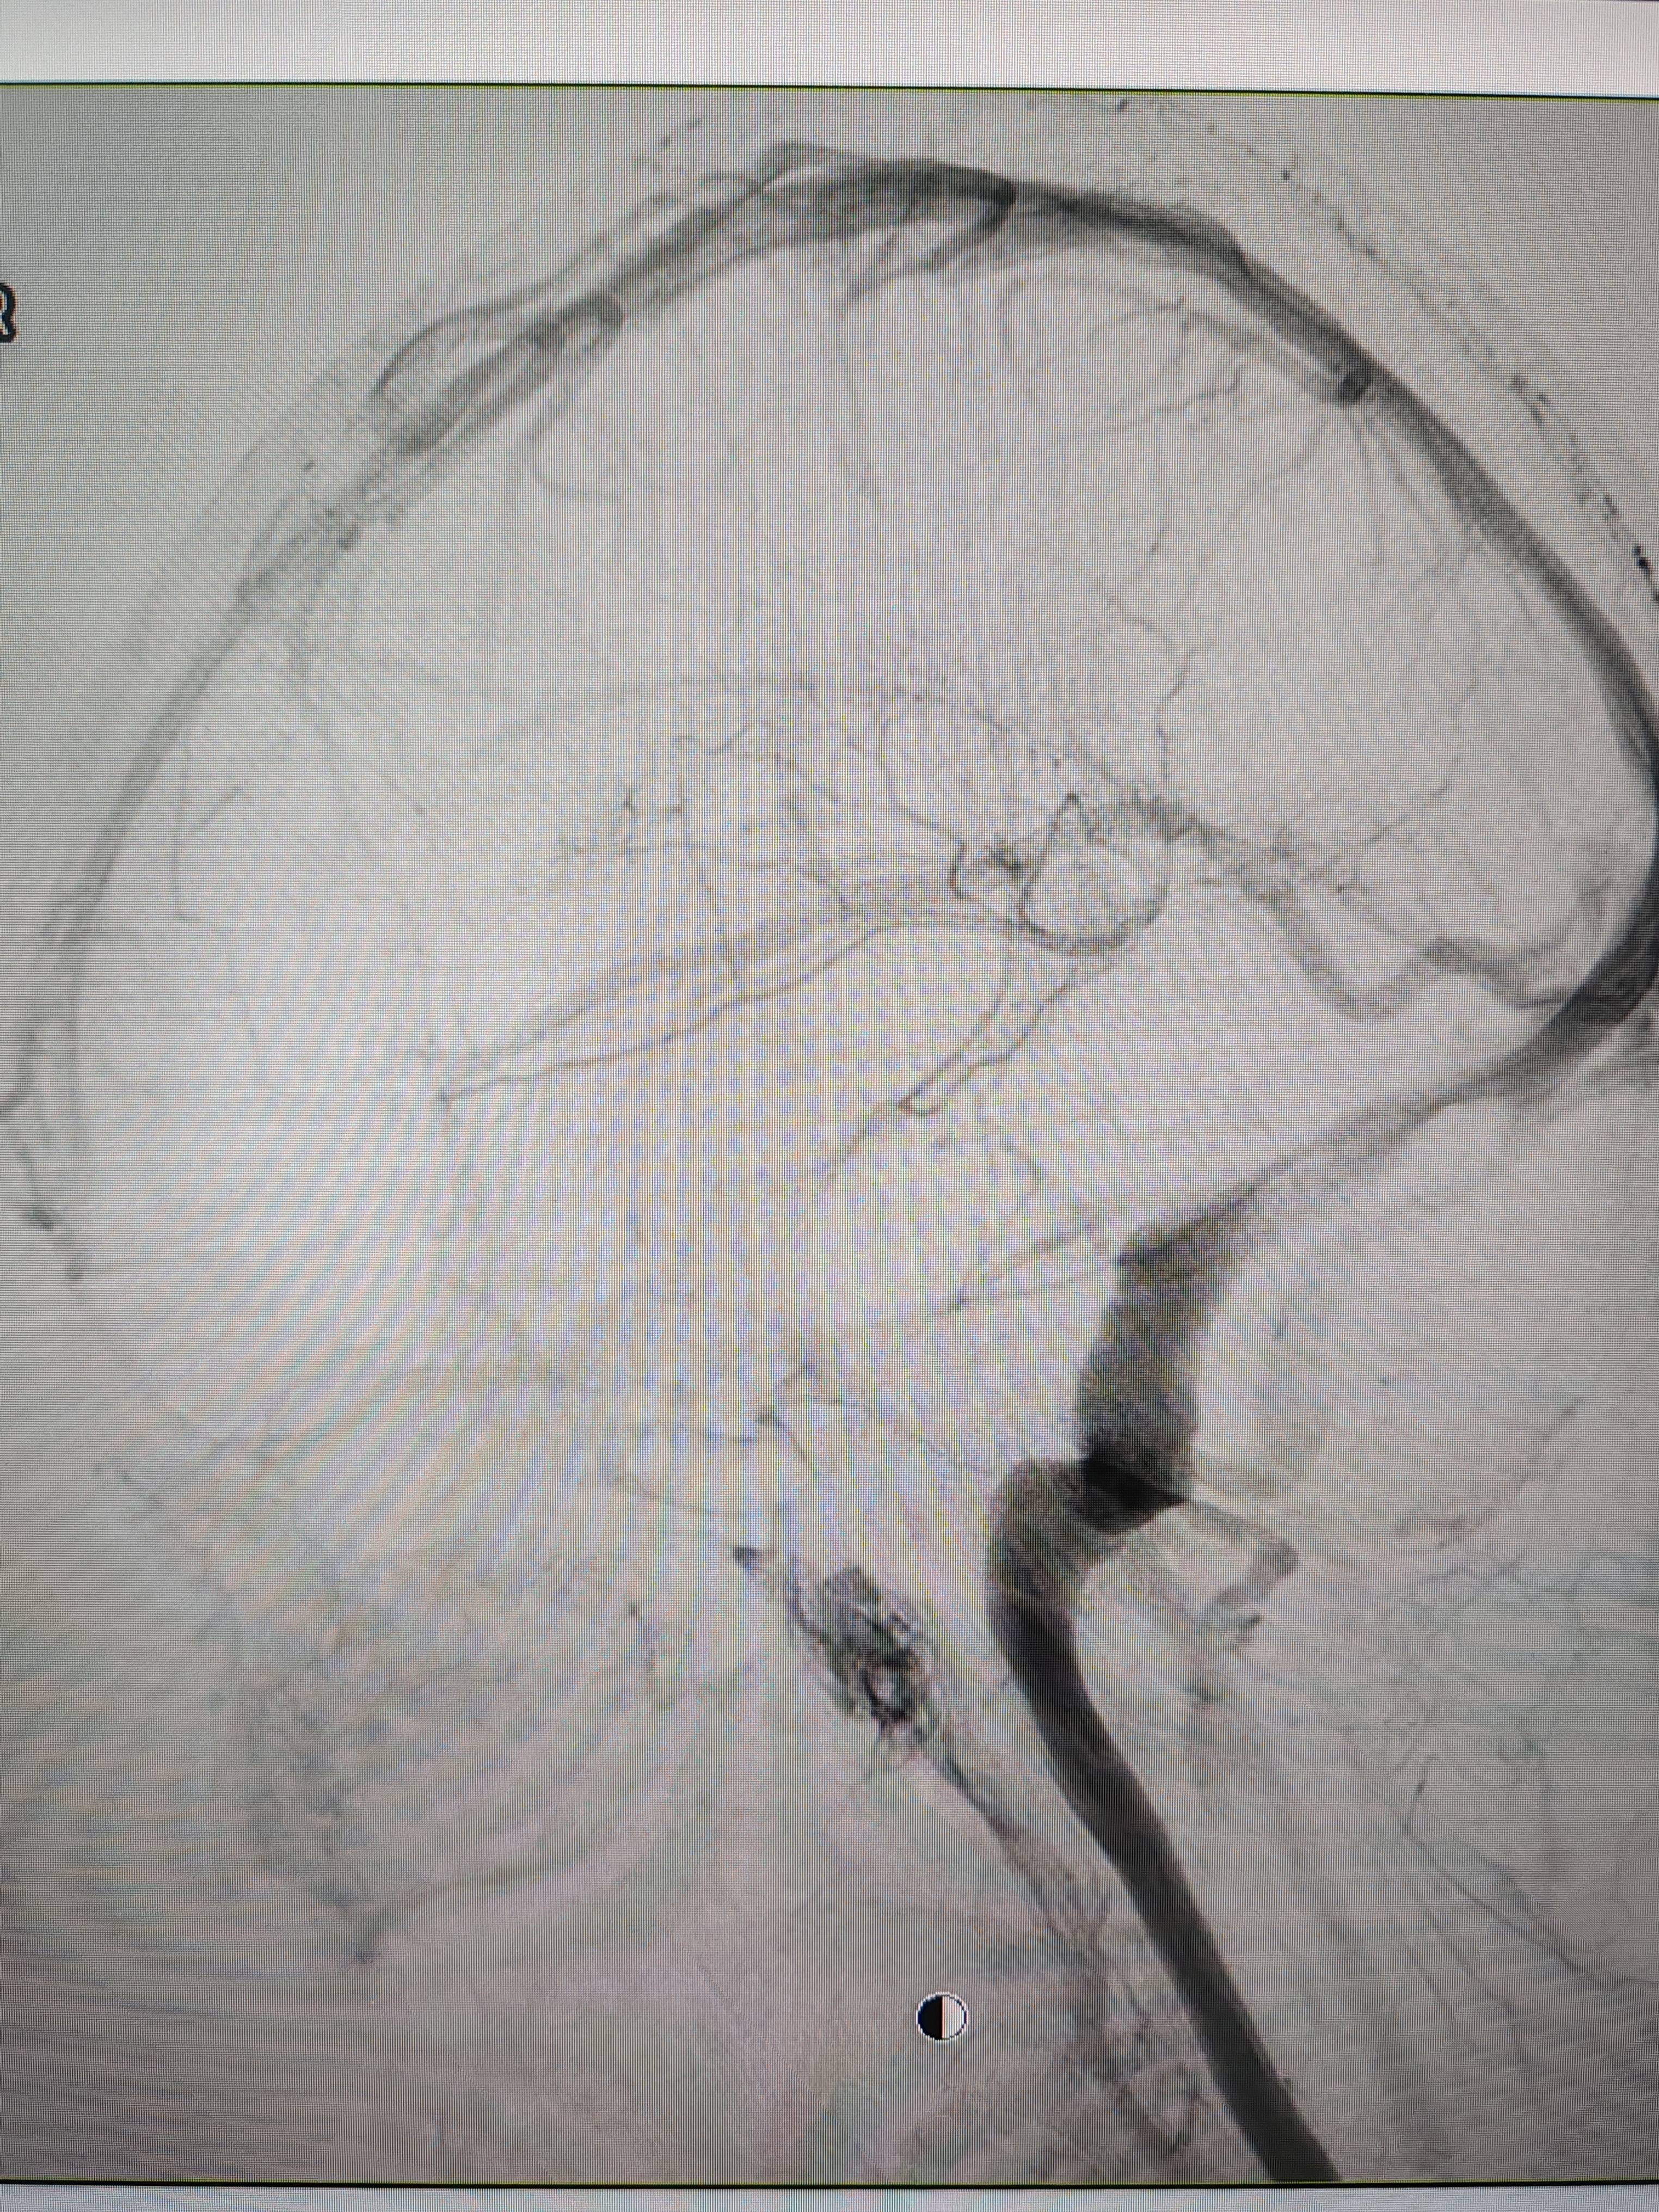

患者造影图像显示,其耳侧静脉窦狭窄证券市场基础知识。 南方+ 欧阳少伟 拍摄

李宝民举例说,通过查体、CT、造影等影像技术的检查,患者赵女士是由于静脉窦狭窄,导致缓慢的静脉血流也出现“湍流”现象,其拐弯、打漩涡、回流产生的声响,又顺着骨传导,传至耳蜗处,进而让患者出现搏动性耳鸣的症状证券市场基础知识。